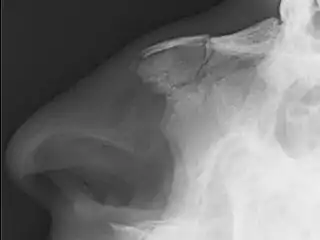

Fractura nasal

Una fractura nasal,[1] comúnmente conocida como nariz rota, es una fractura de uno de los huesos de la nariz. Los síntomas pueden incluir sangrado, hinchazón, moretones e incapacidad para respirar por la nariz. Pueden complicarse con otras fracturas faciales o un hematoma septal.

Las causas más comunes incluyen asalto, trauma durante deportes, caídas y colisiones de vehículos motorizados. El diagnóstico generalmente se basa en los signos y síntomas y, en ocasiones, puede confirmarse mediante una radiografía simple.